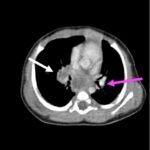

Infant tuberculosis (TB) is a rare but potentially deadly infection and difficult to diagnose, especially in infants who may present with non-specific symptoms. Here, we report a case of an United States-born term infant with community-acquired miliary TB and no confirmed TB exposure history. The patient initially presented with respiratory distress at seven weeks of life with chest radiograph showing a right lower lobe (RLL) infiltrate. After failing multiple courses of treatment for community-acquired pneumonia and developing growth faltering, the patient had imaging findings suggestive of TB infection with CNS involvement. The diagnosis of TB was confirmed by QuantiFERON and purified protein derivative (PPD). In infants who fail conventional treatment for bacterial pneumonia, the differential should be broadened to consider alternative etiologies. Additionally, brain imaging should be performed in cases of disseminated TB despite negative cerebrospinal fluid (CSF) studies since these patients are at high risk of central nervous system (CNS) involvement.